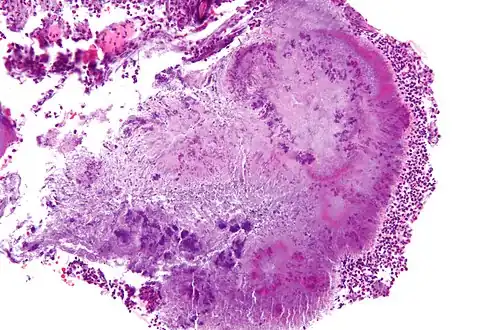

Actinomycota are normally present in the gums, and are the most common cause of infection in dental procedures and oral abscesses. Many Actinomyces species are opportunistic pathogens of humans and other mammals, particularly in the oral cavity.[7] In rare cases, these bacteria can cause actinomycosis, a disease characterized by the formation of abscesses in the mouth, lungs, or the gastrointestinal tract.[8] Actinomycosis is most frequently caused by A. israelii, which may also cause endocarditis, though the resulting symptoms may be similar to those resulting from infections by other bacterial species.[9][10] Aggregatibacter actinomycetemcomitans has been identified as being of note in periodontal disease, especially aggressive and localized form.[11]

The genus is typically the cause of oral-cervicofacial disease. It is characterized by a painless "lumpy jaw". Lymphadenopathy is uncommon in this form of the disease. Another form of actinomycosis is thoracic disease, which is often misdiagnosed as a neoplasm, as it forms a mass that extends to the chest wall. It arises from aspiration of organisms from the oropharynx. Symptoms include chest pain, fever, and weight loss. Abdominal disease is another manifestation of actinomycosis. This can lead to a sinus tract that drains to the abdominal wall or the perianal area. Symptoms include fever, abdominal pain, and weight loss.[12] Actinomyces species have also been shown to infect the central nervous system in a dog "without history or evidence of previous trauma or other organ involvement."[13]